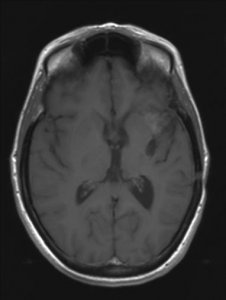

Een astrocytoom graad III groeit onbehandeld snel door in het omliggende hersenweefsel; de ziektegeschiedenis is daarom meestal relatief kort. De meeste patiënten zijn tussen de 30 en 50 jaar oud, iets vaker mannen dan vrouwen. Een MRI toont meestal een grillige, slecht begrensde tumor die met contrast kan aankleuren. De diagnose moet gesteld worden door onderzoek van het weefsel.

'Hoe is het mogelijk, dit kan niet, dit is bizar, zoiets heb ik nog nooit gezien maar het is waar'. Dit waren de woorden van de neuro-oncoloog. Mijn vriendin Ineke en ik bogen ons naar haar computer waar het onverklaarbare resultaat stond. Op de MRI-scan was te zien dat de kwaadaardige tumor zich had teruggetrokken. De tumor had een donkere holte met een grillige tumorrand achtergelaten. De neuro-oncoloog benadrukte nog eens dat het echt heel bijzonder was en dat zij en de radioloog voor een raadsel stonden. Ik vroeg haar wat dit betekende voor de prognose van mijn levensverwachting. Ze zei dat er nog één of misschien zelfs twee jaar zou bijkomen. Meer durfde ze er ook niet over te zeggen.

De MRI-scan van oktober 2009

De MRI scans van 2006 en 2007 zijn niet correct geïnterpreteerd. Wat toen als tumorgroei werd gezien blijkt nu een reactie van de bestraling te zijn. De chemokuur was overbodig omdat de tumor niet groeide. Wat je nu ziet is de tumor die enigzins gegroeid lijkt, maar dat is niet zeker. Als het zeker is moet je overwegen om opnieuw bestraald te worden. Meer patienten zijn ook met de verkeerde boodschap (dat de tumor groeit) naar huis gegaan,ook in andere ziekenhuizen.